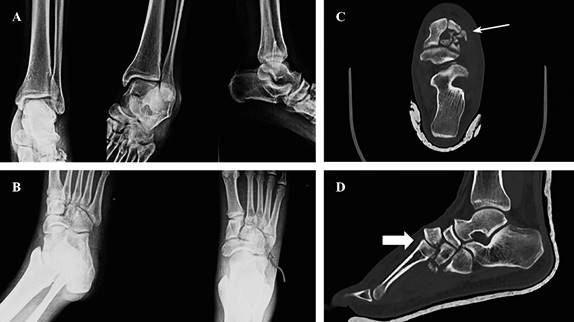

En pacientes con lesiones de alta energía del mediopié: fracturas/luxaciones y significativo daño de tejidos blandos, el protocolo de manejo por etapas incluye la fijación externa. Ésta permite recuperar la longitud y alineación de las columnas óseas favoreciendo la recuperación de las partes blandas, antes de realizar la fijación interna definitiva (Figuras 5 y 6).55,56

Figura 5: Paciente con luxofractura de Lisfranc compleja del pie. A) Radiografía con serie de trauma con irregularidad en escafo-cuneiforme. B) Radiografía de pie con fractura de cuboides (flecha curva). C) Tomografía axial; muestra conminución de segundo y tercer cuneiforme (flecha). D) Tomografía sagital; se observa luxofractura dorsal cuneiforme (flecha).